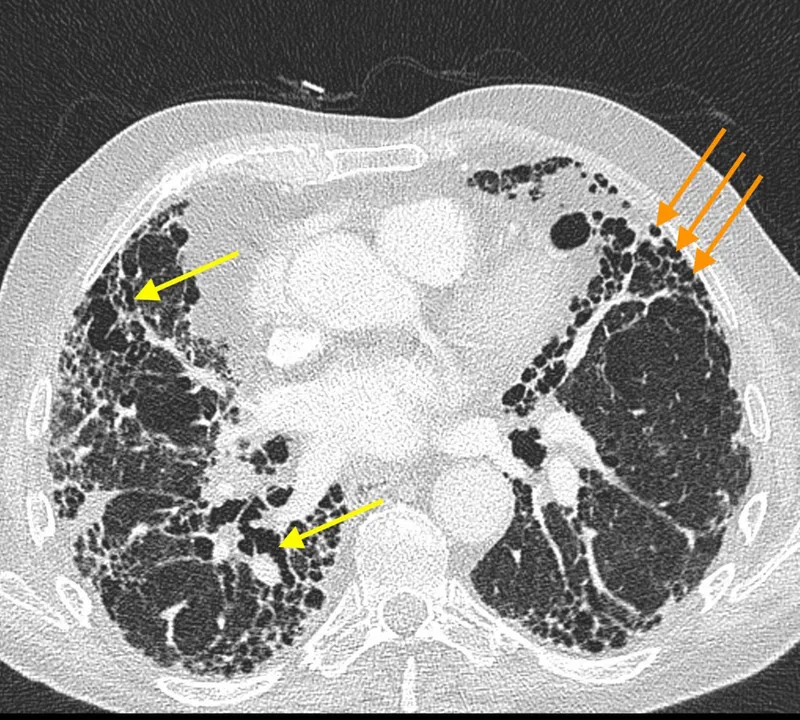

- Honeycombing: Clustered, stacked subpleural cysts (typically 3-10 mm diameter, <3 mm walls); key for UIP.

- Traction bronchiectasis/bronchiolectasis: Irreversible airway dilatation due to adjacent fibrosis.

- UIP Pattern (HRCT): Basal, subpleural, reticular pattern; honeycombing is hallmark. +/- traction bronchiectasis. Absence of features suggesting alternative diagnoses.

- Acute/Subacute: Centrilobular GGO nodules, mosaic attenuation (air trapping on expiration).

- Chronic: Fibrosis (often mid/upper zone or diffuse), honeycombing (can mimic UIP but distribution differs), significant air trapping.

⭐ "Three-density pattern" ("headcheese sign": normal lung, GGO, air trapping) on HRCT strongly suggests subacute HP.